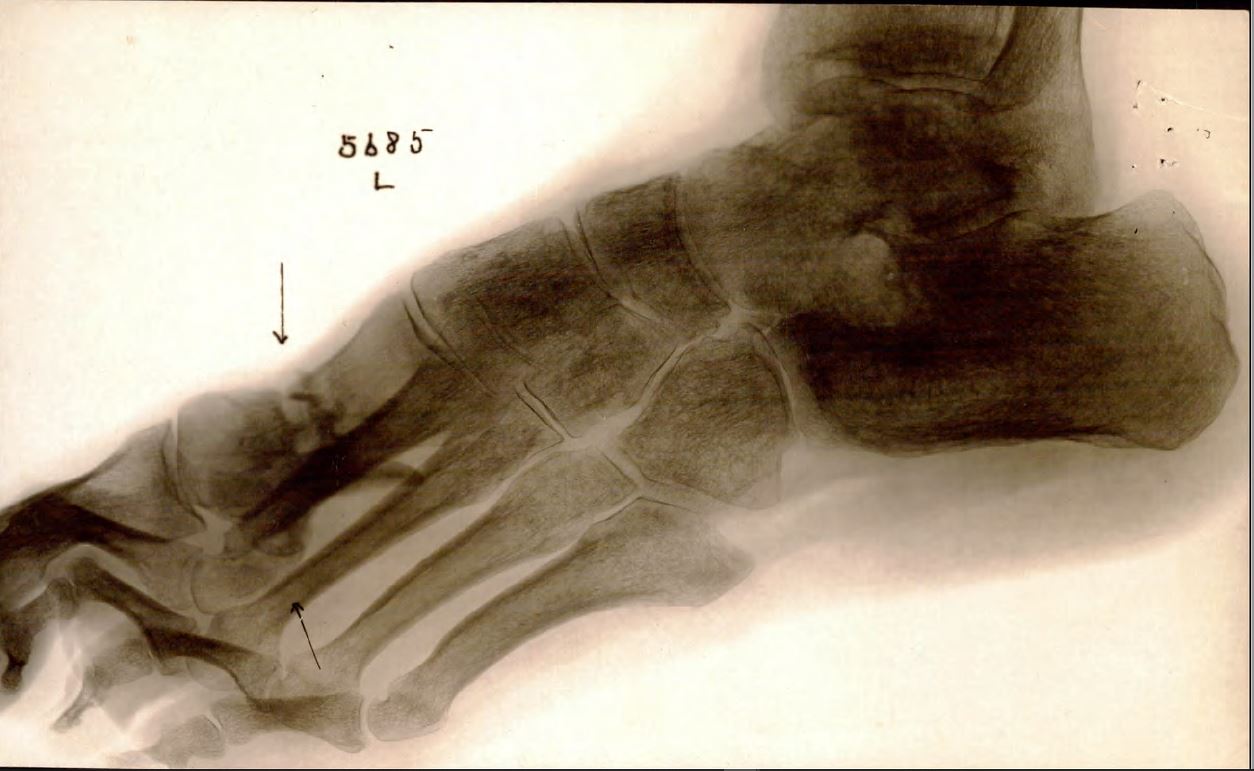

Xray of foot with foreign body 2 Like Loading... Leave a comment Cancel reply Δ This site uses Akismet to reduce spam. Learn how your comment data is processed.